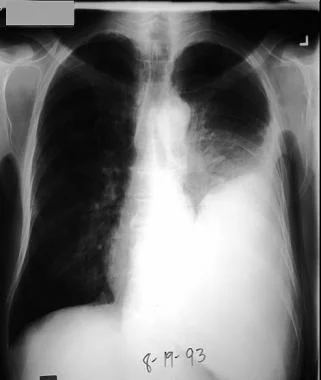

1. 胸片检查

胸部X线片常显示有大量的胸水。对疑似肺炎旁胸腔积液的患者。

图1 抗生素治疗肺炎球菌性肺炎4天,出现左侧胸腔积液。患者发热

、左侧胸痛

和呼吸困难

加重。胸腔穿刺培养显示为肺炎链球菌。